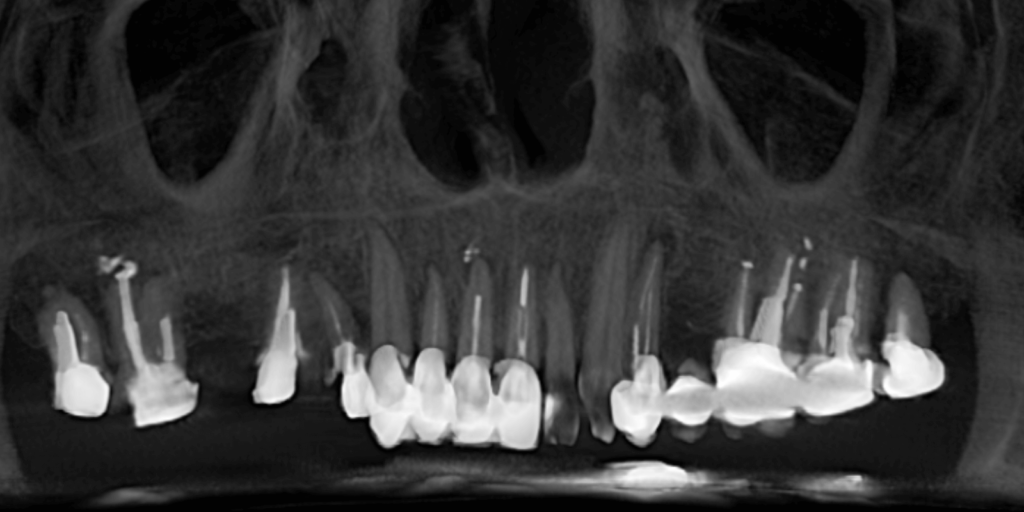

Что было в начале: мостовидные протезы, держащиеся «на честном слове». Боль с одной стороны челюсти, невозможность нормально жевать. Часть зубов под коронками оказалась разрушенной. Некоторые каналы были недолечены.

На верхней челюсти снять мостовидные протезы и удалить 4 зуба. Выполнить повторное лечение корневых каналов ("реэндо"). Также установить импланты Straumann BLX.

Осмотр. Диагностика. План лечения

Нижняя челюсть

Верхняя челюсть